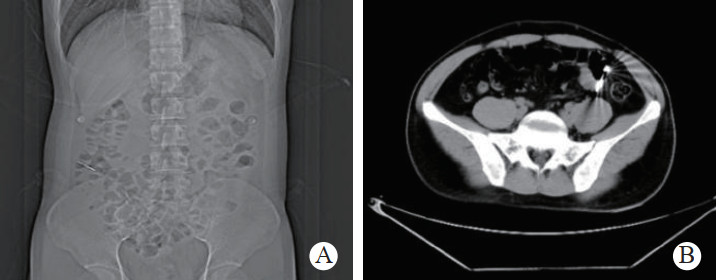

1 一般资料患者,男性,32岁,职员,因“误吞金属钉状物7 d”就诊。患者7 d前误吞入金属钉状物一根(大小约3 cm),患者无明显不适症状,未诊治。4 d前出现下腹隐痛,行急诊全腹CT检查,见图 1,行急诊胃镜检查未见明显异物。后复查腹部CT示异物进入小肠内(图 2),普外科会诊建议随访。2 d前复查腹部CT(图 3),继续保守治疗。1 d前患者为行异物取出入院,复查腹部CT可见异物至结肠内(图 4)。急诊予以聚乙二醇电解质散导泻清肠,行无痛肠镜下异物取出术。本文已通过本院伦理委员会审批,伦理审批号为:(2021)伦审研第(0252)号,并通过免除知情同意申请。完善术前检查,进行药物导泻清肠时,关注患者有无腹痛等现象,以免因服用药物清肠,肠蠕动加快,尖锐异物在消化道内随蠕动前行,尖端嵌插在肠壁中而停滞不前,并随着后方内容物的推进,加深尖锐异物刺入肠壁,最终导致穿孔及出血的发生。本例患者安置在独立单人间进行肠道准备,不定时进行腹部查体及观察排泄物的性状,早期发现穿孔、出血指征,以便尽早进行外科手术干预。与此同时,内镜中心医护人员联合外科、放射科、麻醉科医生制定诊疗方案,若发生此类情况,立即予急诊行腹部X线或CT检查,一旦确定出现穿孔或出血等情况,即刻行急诊手术治疗。

| 图 3 腹部CT示升结肠起始部管腔内致密影,约3.2 cm, 周边放射状明显,邻近肠系膜未见渗出和积气 |